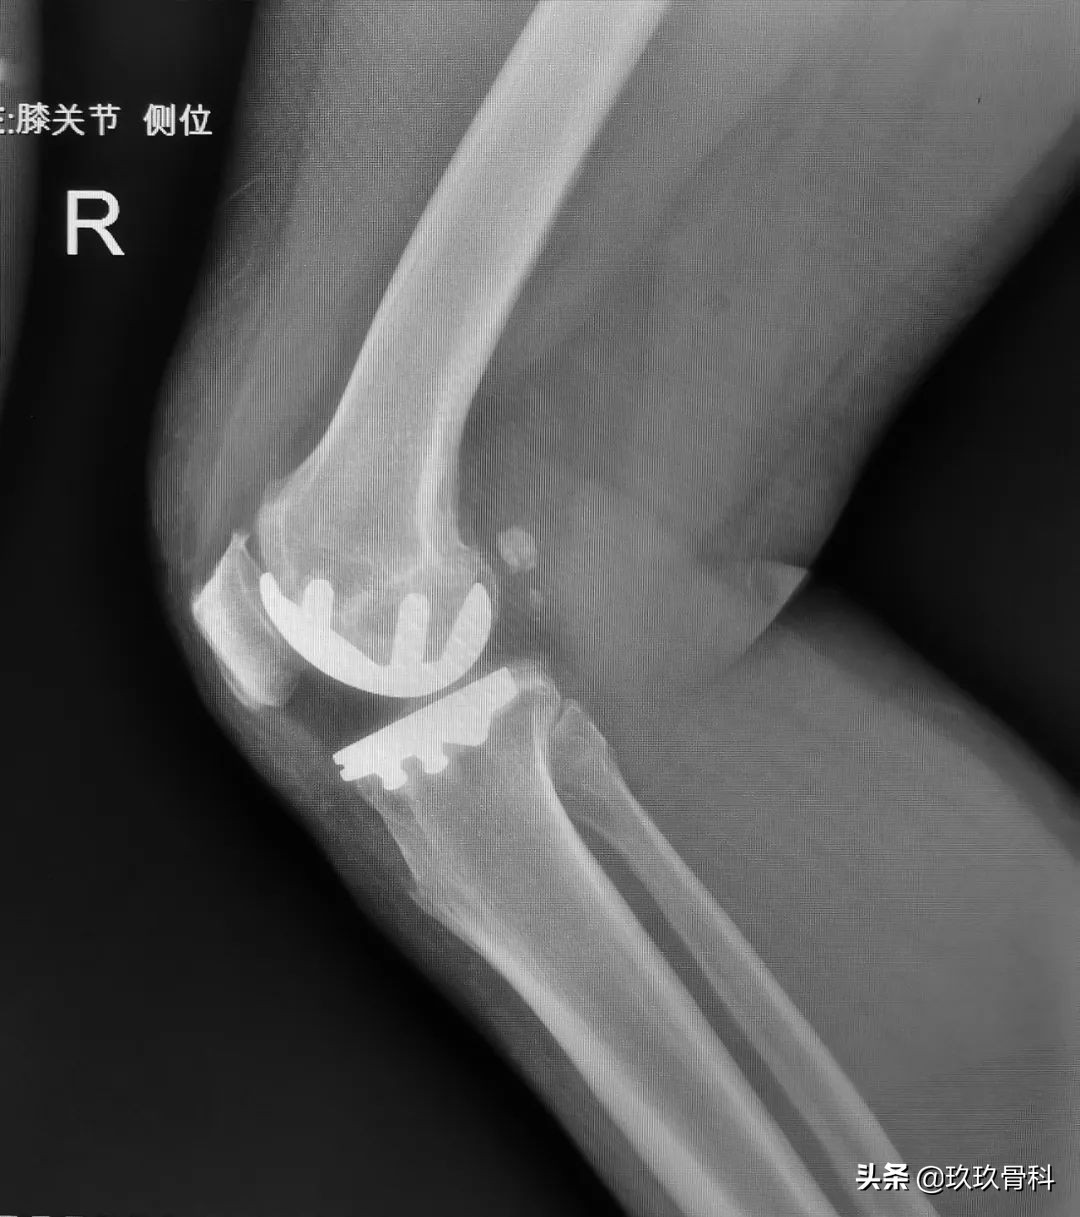

术前影像

术后影像

辅助检查: 双膝关节正侧位示:双膝关节退行性关节炎。

入院后,于天彦主任展开了详细的查体,并结合影像学检查,初步诊断为双膝骨性关节炎。经过于天彦主任团队周密的手术方案讨论和制定,考虑患者年龄和身体状况及工作情况,最终决定拟行“双膝单髁置换术”。